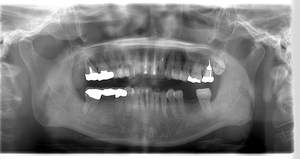

レントゲン写真

- 透過像

| 年齢 | 50代・男性 |

|---|---|

| 主訴 | 右下歯が疼く |

| 治療内容 | ・右下6番インプラント ※1:FGG(遊離歯肉移植術)とは、足りない歯ぐきを上顎から上皮を切り取り移植する外科手術 |

| 治療費 | 合計:902,000円(税込) ■内訳 |

| 治療期間 | 9ヵ月 |

| 治療方針 | 右下の当該歯は歯根破折により保存不可能と診断しました。歯周疾患も伴っていたため抜歯後に骨吸収※1が大きく起こることが予測できました。チタンメッシュ併用骨再生誘導法(GBR※2)を選択しインプラント埋入と同時に行い自然な歯槽骨のラインを再現しました。またGBRを行う際にインプラント辺縁の付着歯肉の減少が起こる為、遊離歯肉移植術(FGG※3)を行い清掃性を考慮した形態に仕上げました。 ■治療方針の解説 治療した右下の歯をレントゲンで撮影したところ根本の部分に黒く写る箇所があり「根尖性慢性周囲炎※1」と診断。また歯周病も進行していました。 ※1 骨吸収・・・歯槽骨という歯を支える骨がなくなっていくこと |

| 担当者所見 | 主訴の右下だけでなく歯茎の腫れ、発赤があり不良補綴や不良充填など他にも治療箇所が多数ありました。プラークコントロールが不良であった為まずはブラッシング指導を行いセルフケアの重要性を理解していただくところからスタートしました。 右下6番の歯はインプラント治療を行なった結果審美的にも機能的にも患者様の満足を得ることができました。骨造成と歯肉移植も行なった為インプラントを支える十分な歯周組織の獲得ができたと思っております。 |